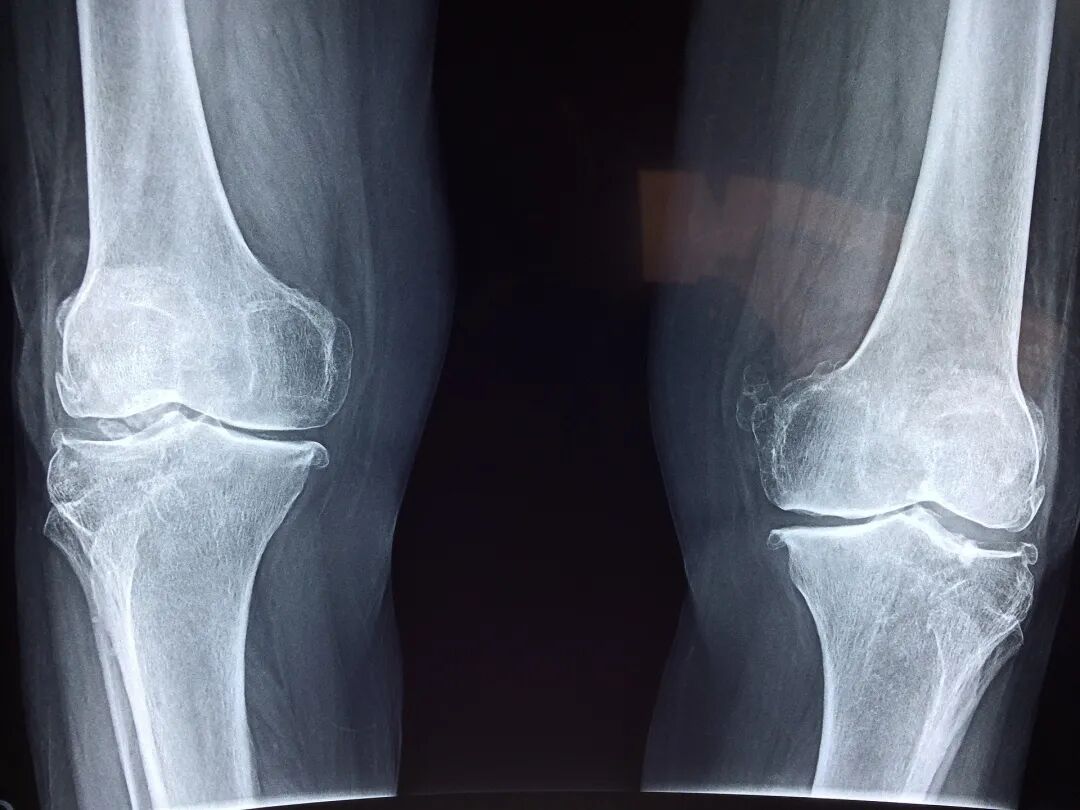

本次主要针对骨科创伤、血液透析两大类医用耗材、以不低于年采购量70%的约定采购量进行以量换价。根据公布的信息来看,骨科创伤产品的采购数量约为11.8万个,血液透析产品采购数量为577.3万个,总采购量为589.1万个。

据《淄博晚报》报道,本次采购降价空间非常大,如某公司生产的普通接骨板-普通重建接骨板,降价前平均销售价2503.4元/块,经谈判后价格降至150元/块,降价幅度94%;某公司生产的螺旋刀片式股骨近端髓内钉,降价前平均销售价17400元,经谈判后价格降至2600元,降价幅度85%。

与此同时,第一轮报价1078元的弹性髓内钉,层层还价后,最终也报出了777元的最低价。现场参与竞标的企业代表更是直言:“已经不是见血见肉的砍价了,简直就是见骨头。”